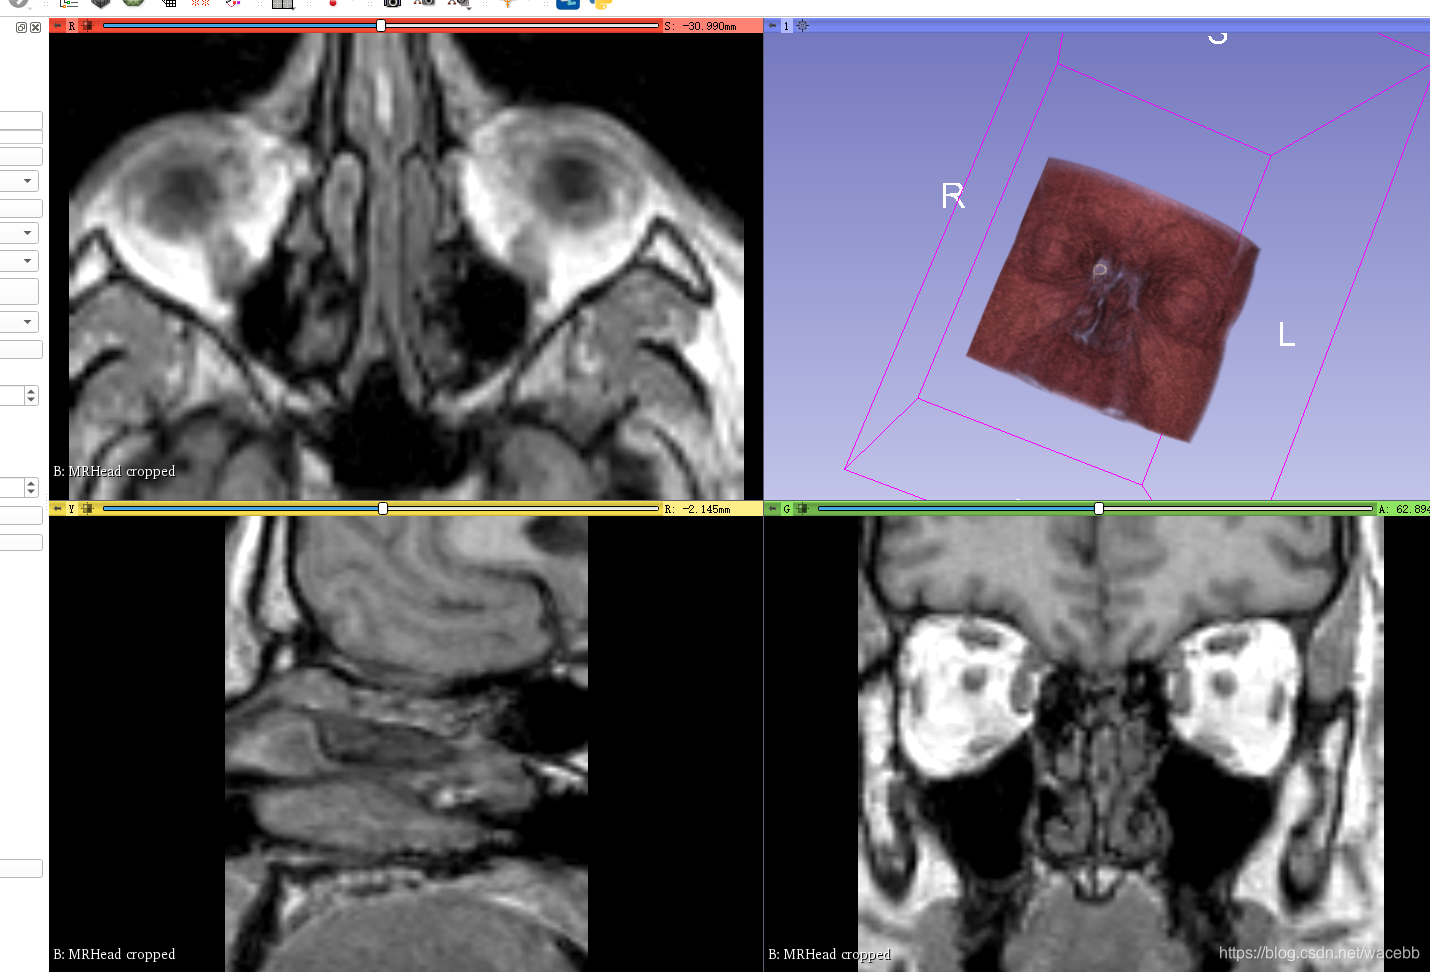

Roi 意思 影像 (99) 사진